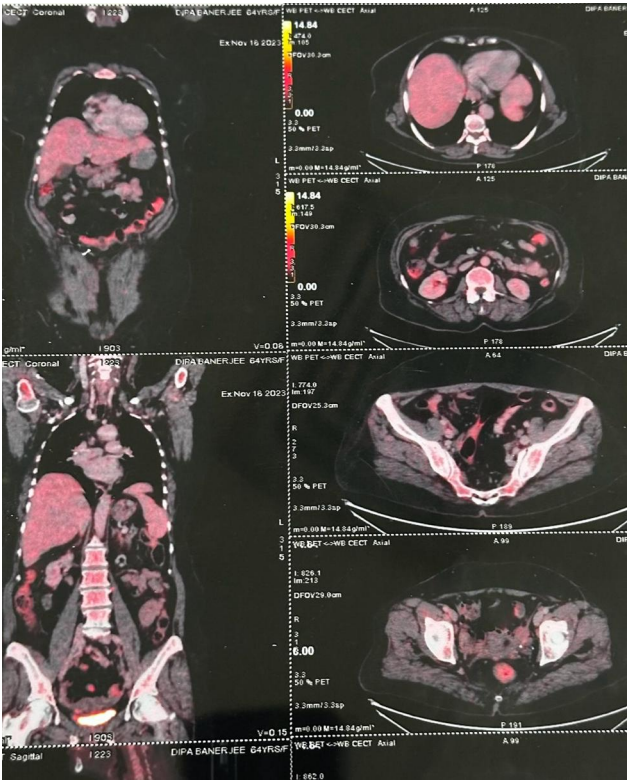

Fig 3

Fig 4

Figure 3

Figure 4